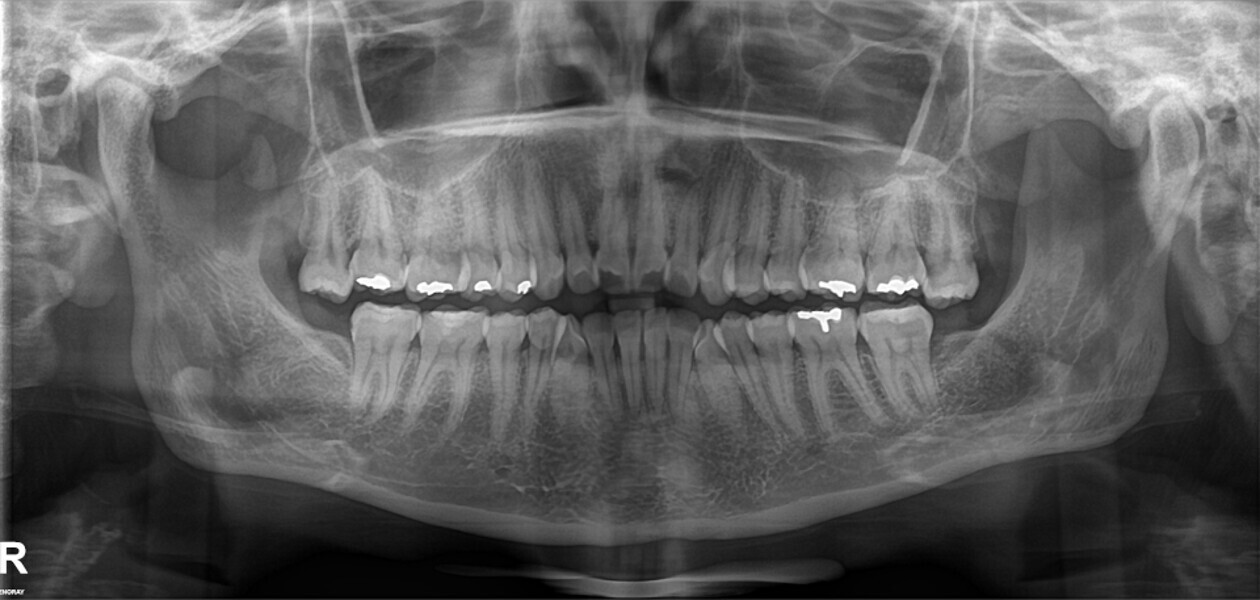

A 35-year-old female patient presented with crowding, muscle and joint pain, and headaches upon awakening. Examination found a skeletal Class I with crowding and bimaxillary protrusion. Facial examination showed a convex profile with protruded lips and a square face shape, intensified on smiling (Figs. 1–4). She reported bruxism, and bilateral masseteric hypertrophy was observed, but there was no alteration of the temporomandibular joints.

Before the aligner treatment began, the maxillary and mandibular second premolars were extracted to create space. With orthodontic treatment, distalisation of the anterior teeth was achieved by employing maximum mandibular anchorage and moderate maxillary anchorage (Figs. 5–7). At the end of the treatment, a stable bilateral Class I occlusion had been achieved, as well as normal inclination and retrusion of the anterior teeth, consequently improving the profile (Figs. 8–10).